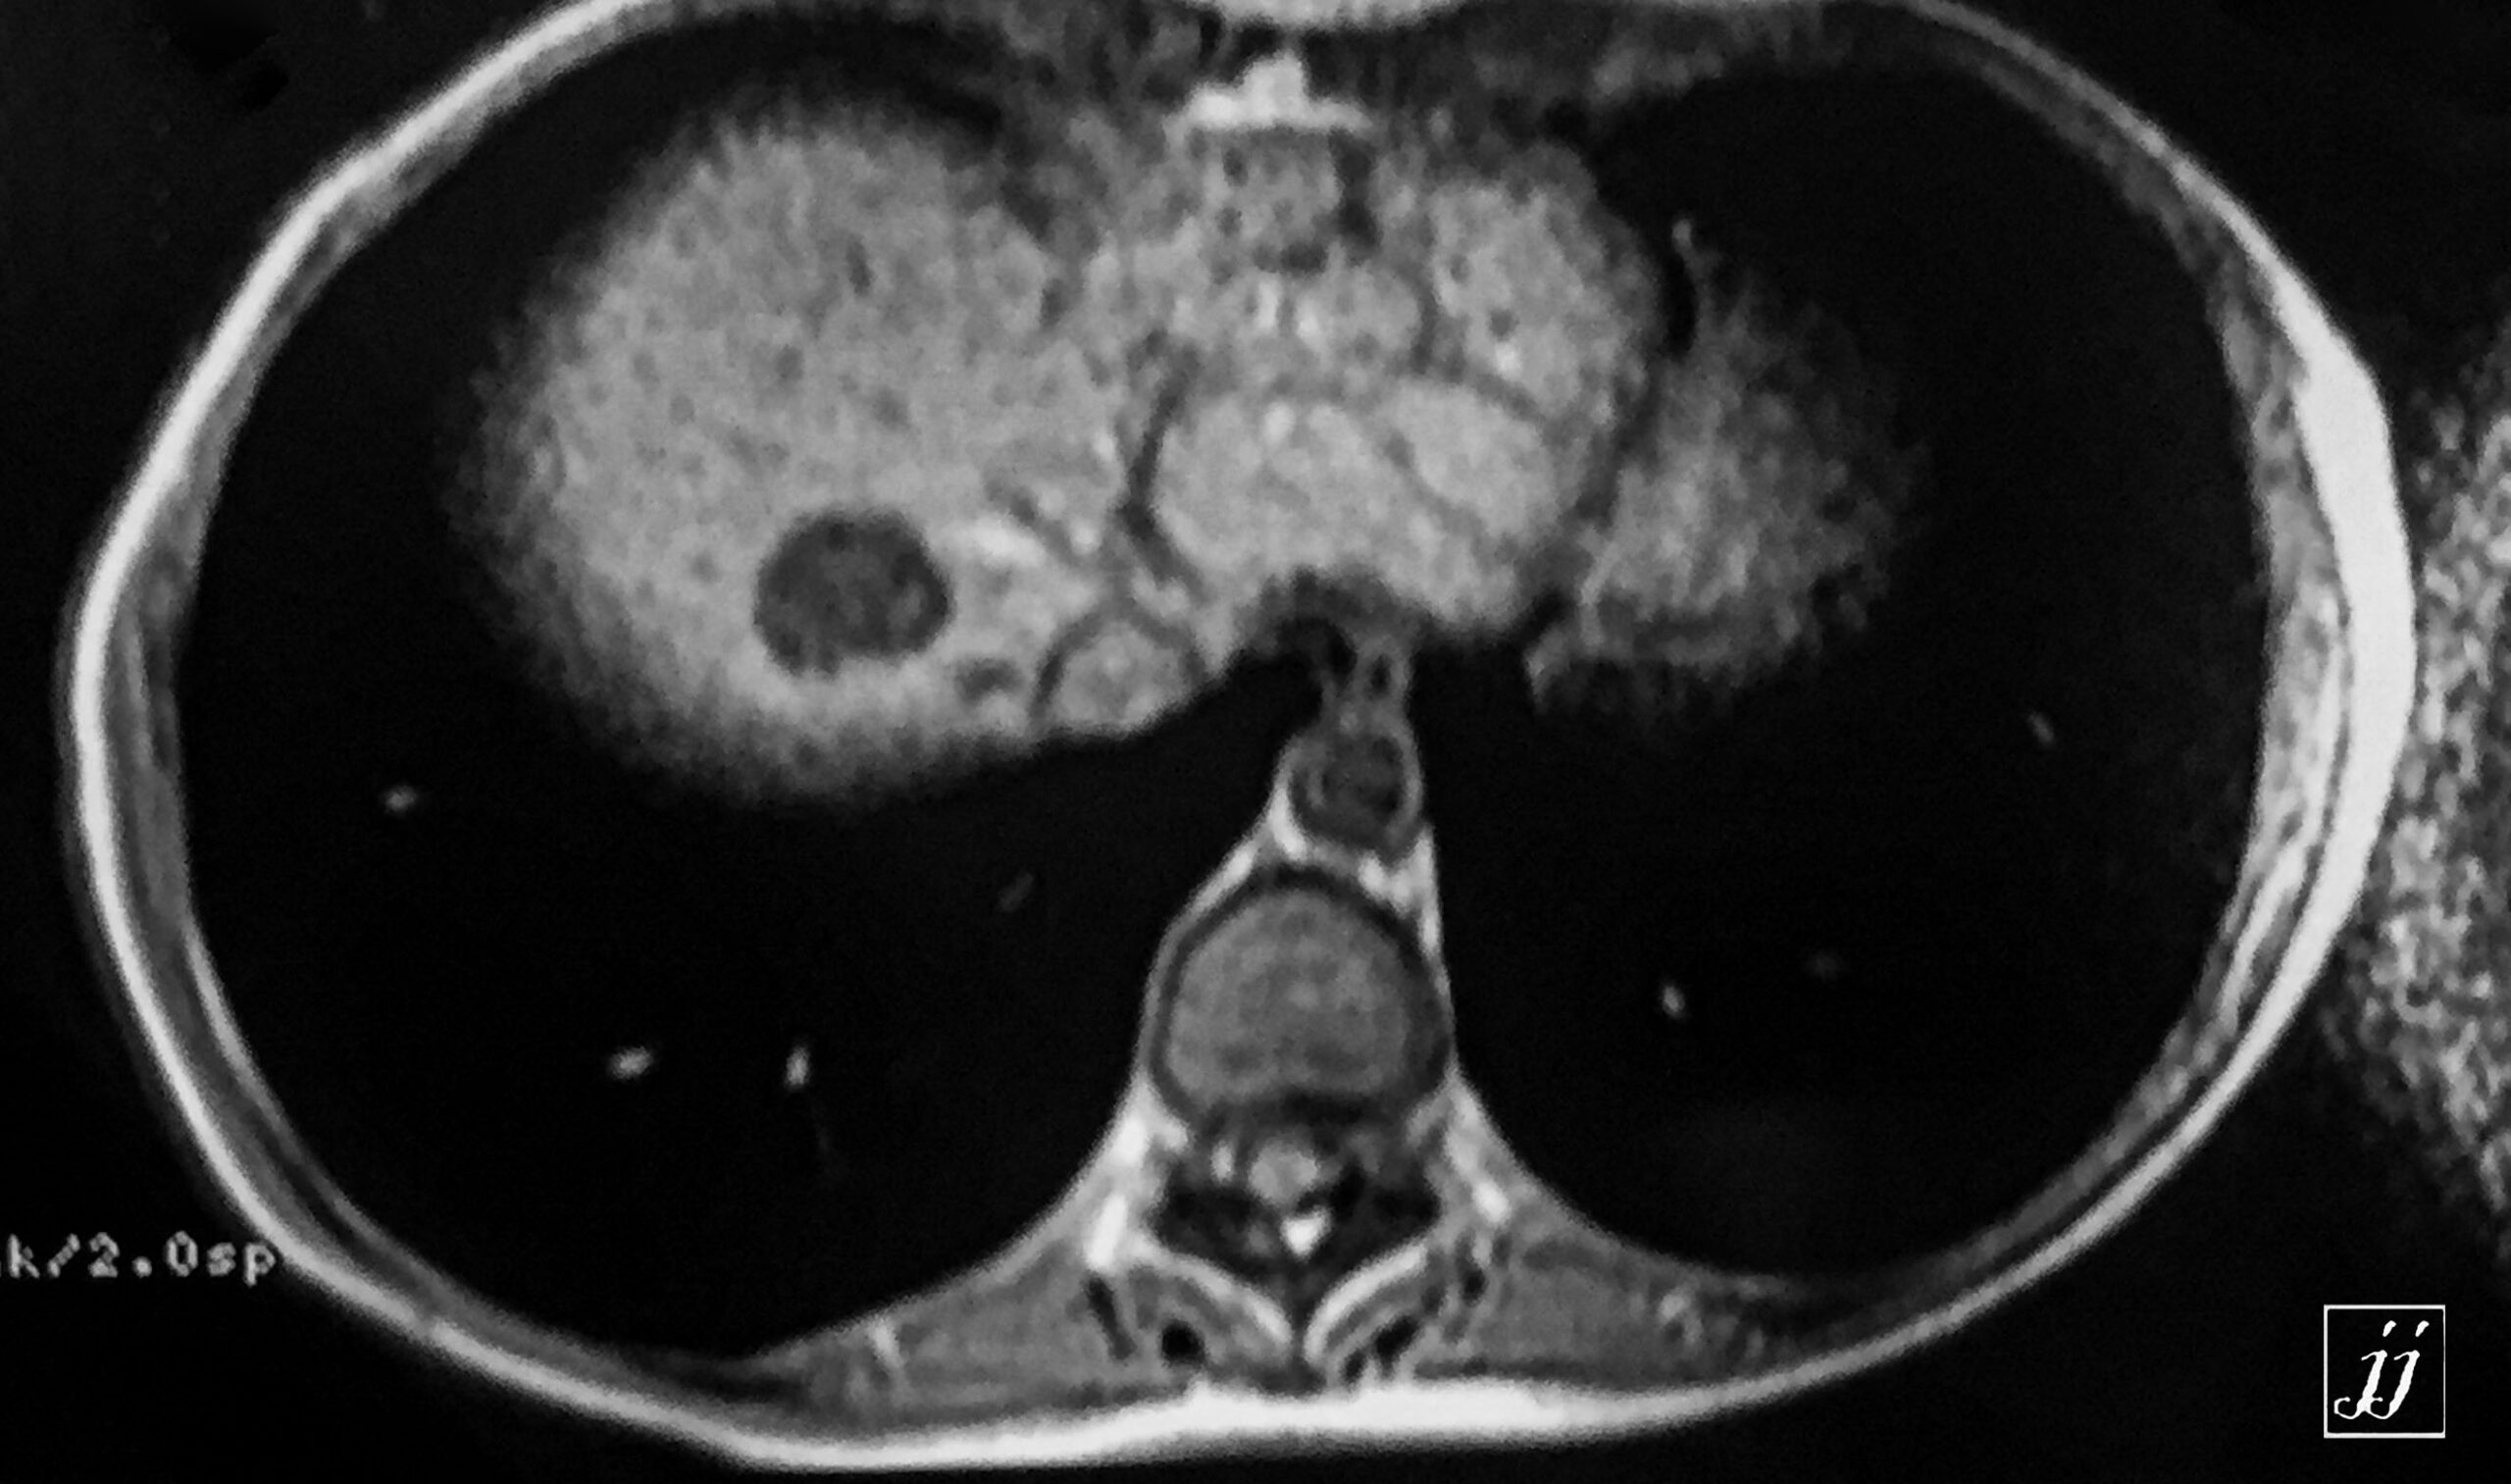

Abdomen- multiple liver cyst (8)